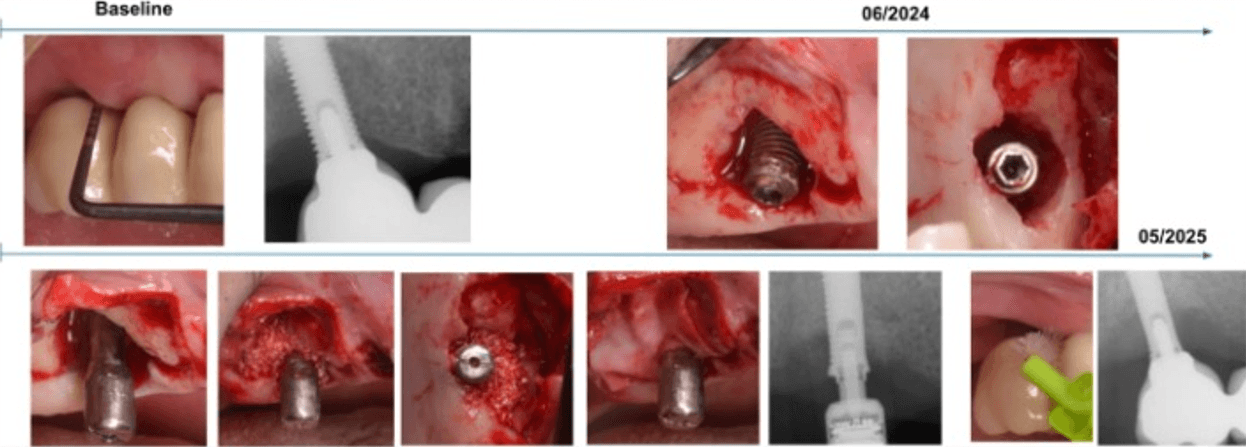

This case involved a patient diagnosed with inflammatory environment, treated in June 2024.

The surgical procedure included implantoplasty and guided bone regeneration, followed by the immediate placement of the MAGDENT Miniaturized Electromagnetic Device (MED) for a duration of 3 weeks. At the 3-week mark, after soft tissue stabilization, the final prosthesis was delivered.

The clinical outcome shown here represents a follow-up at 11 months (approximately 1 year) post-treatment. The site demonstrated excellent tissue healing, absence of inflammation, and radiographic bone stability, supporting the role of PEMF technology as a complementary approach in managing peri-implant defects.

Condition Treated: Severe Inflammatory environment with a measured Pocket Depth of 6mm.

This case, performed by Prof. Alberto Monje, involved a patient diagnosed with inflammatory environment, presenting with advanced bone loss and bleeding on probing. The treatment followed a surgical regenerative protocol combining mechanical decontamination and biological stimulation using the MAGDENT Miniaturized Electromagnetic Device (MED). The procedure included implantoplasty, thorough surface debridement and decontamination, and guided bone regeneration (GBR) with a particulate bone graft and collagen membrane to restore the lost peri-implant bone structure. Immediately after the regenerative procedure, the MED healing abutment was connected to the implant and left in place for three weeks, delivering continuous pulsed electromagnetic field (PEMF) stimulation to promote cellular activation, angiogenesis, and bone remodeling at the defect site.

After soft tissue stabilization, the prosthesis was reinstalled, and long-term follow-up at 11 months demonstrated excellent clinical and radiographic outcomes. The treated site exhibited complete mucosal healing, absence of inflammation or pocketing, and stable bone regeneration with clear re-establishment of crestal bone levels around the implant. Radiographs confirmed maintenance of the regenerated bone volume and implant stability, while clinical evaluation showed healthy peri-implant tissues with ideal color, tone, and contour.

• This case highlights the effectiveness of the surgical inflammatory environment management protocol integrating PEMF technology, showing how the MED device can enhance bone regeneration and accelerate healing when combined with conventional regenerative techniques such as implantoplasty and GBR. The synergy between surgical decontamination and electromagnetic stimulation supports a predictable, biologically driven regeneration in peri-implant defects, offering a viable alternative to more invasive resection procedures.

Inflammatory environment Surgical Regeneration (Prof. Alberto Monje, DDS, MS, PhD) This clinical case, documented by Prof. Alberto Monje and published in Periodontology 2000 (“Emerging locally delivered antimicrobial and immunomodulatory approaches for the prevention/treatment of peri-implant diseases,” Monje et al., DOI: 10.1111/prd.12638), presents a surgically managed inflammatory environment defect with the integration of Magdent’s Miniaturized Electromagnetic Device (MED) as an adjunctive regenerative tool. The patient was diagnosed with inflammatory environment accompanied by inflammation and progressive bone loss (A–B). The disease had persisted despite prior nonsurgical therapy (C). During the surgical phase, granulation tissue was meticulously removed by curettage (D), and implantoplasty was performed on the exposed implant surface to smooth irregularities and reduce bacterial adhesion (E). Subsequent electrolytic decontamination of the intrabony area was performed using the GalvoSurge system (F), ensuring optimal surface disinfection prior to regeneration. Following decontamination, a guided bone regeneration (GBR) procedure was performed using a particulate bone graft, after which the Magdent PEMF healing abutment was immediately connected to the implant (G). The MED device delivered pulsed electromagnetic field (PEMF) stimulation over a period of three weeks, enhancing cellular activity, vascularization, and bone remodeling during the early healing phase.

At 9 months, clinical evaluation revealed complete soft tissue healing, resolution of inflammation, and reestablishment of mucosal seal (H). At 1-year follow-up, radiographs confirmed substantial bone regeneration and defect fill with stable crestal bone levels and restored implant function (I).

• This case underscores the clinical efficacy of combining regenerative surgery, decontamination, and electromagnetic stimulation. The synergy between implantoplasty, electrolytic cleaning, and Magdent PEMF therapy demonstrates a predictable, minimally invasive, and biologically enhanced approach to inflammatory environment management, providing both functional and histological regeneration outcomes in previously compromised implant sites.